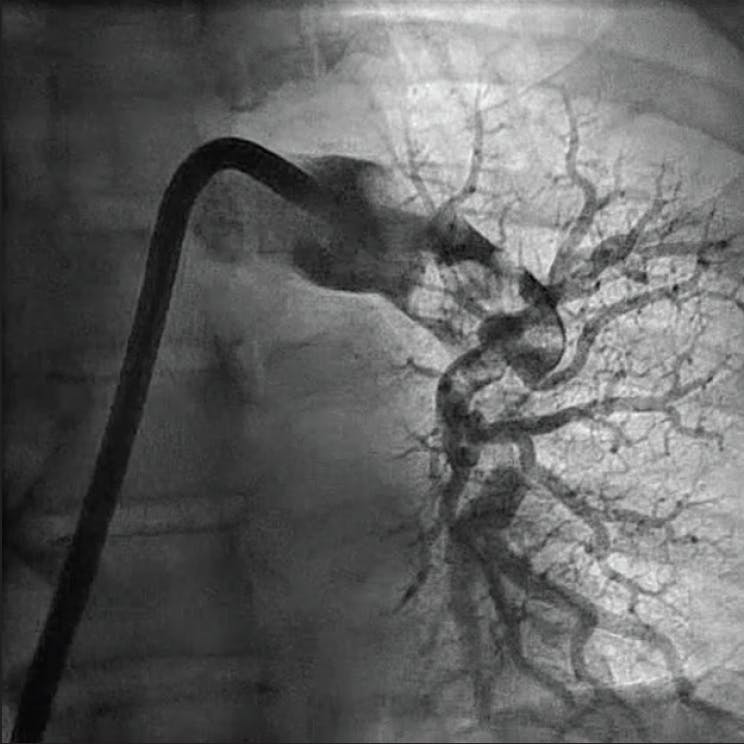

Postprocedure angiography demonstrated resolution of thrombus within the left upper and left lower lobes. The estimated blood loss was minimal at 70 mL. Hemostasis achieved with a purse string suture secured with a three-way stopcock. The access-to-closure procedural time was 31 minutes with a total thrombectomy suction time of 1 minute. The patient was transitioned from high-flow nasal cannula on the procedural table and weaned to room air over the next 2 days. He was discharged from the hospital on postoperative day 3 on appropriate oral anticoagulation.

Figure 2. Postprocedural angiogram of the left PA.